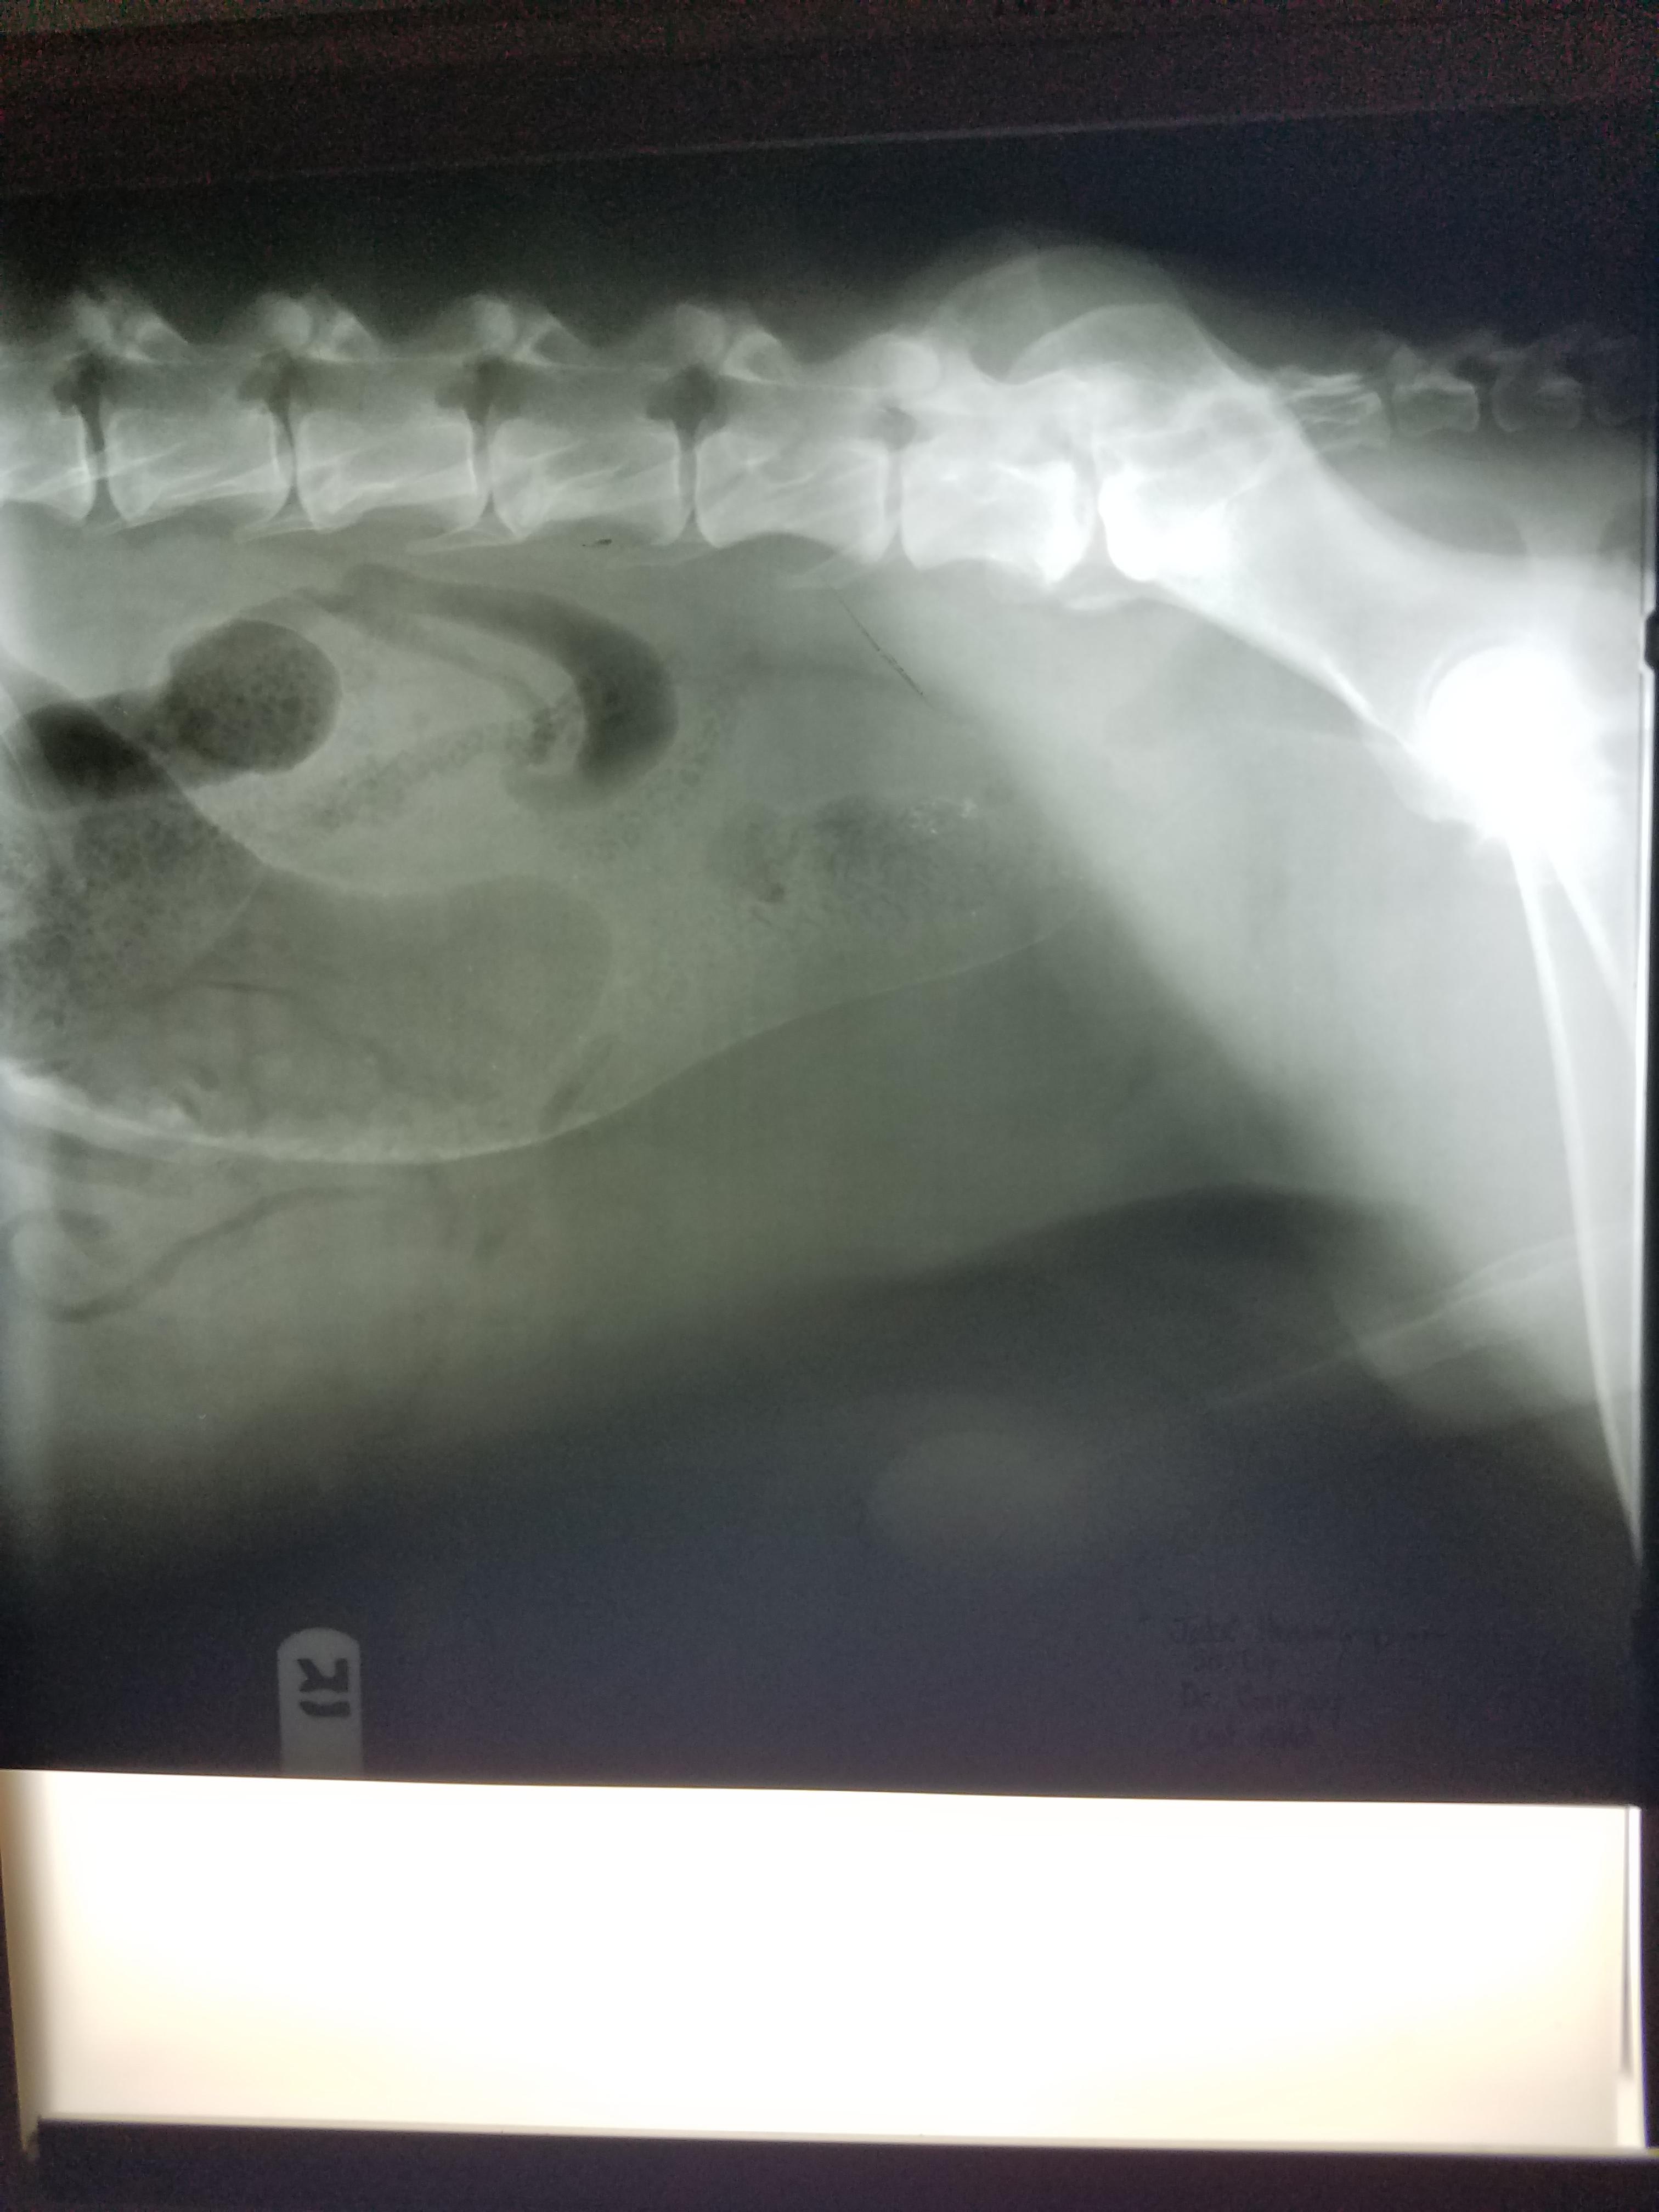

Pet's info: Dog | German Shepherd | Male | unneutered | 8 years and 10 months old | 108 lbs

My Dr was confident my dog had colon/ rectal cancer. We didn't do a fine Needle. Dog was pretty bad. Review attached please. Another Dr here agreed there was a mass. I was told he wouldn't have lost 40 lbs in a year and keep an infection that long. I want to make sure I did the right thing

I am very sorry to hear about your loss of Jake. Based on this information, I believe you made the kindest and most humane decision to let Jake go, as this information all supports a diagnosis of an invasive tumor in a region not amenable to treatment.